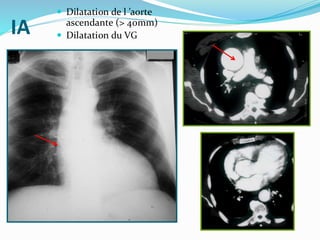

IA

 Dilatation de l ’aorte

ascendante (> 40mm)

 Dilatation du VG

IA  Dilatation del ’aorte ascendante (> 40mm)  Dilatation du VG